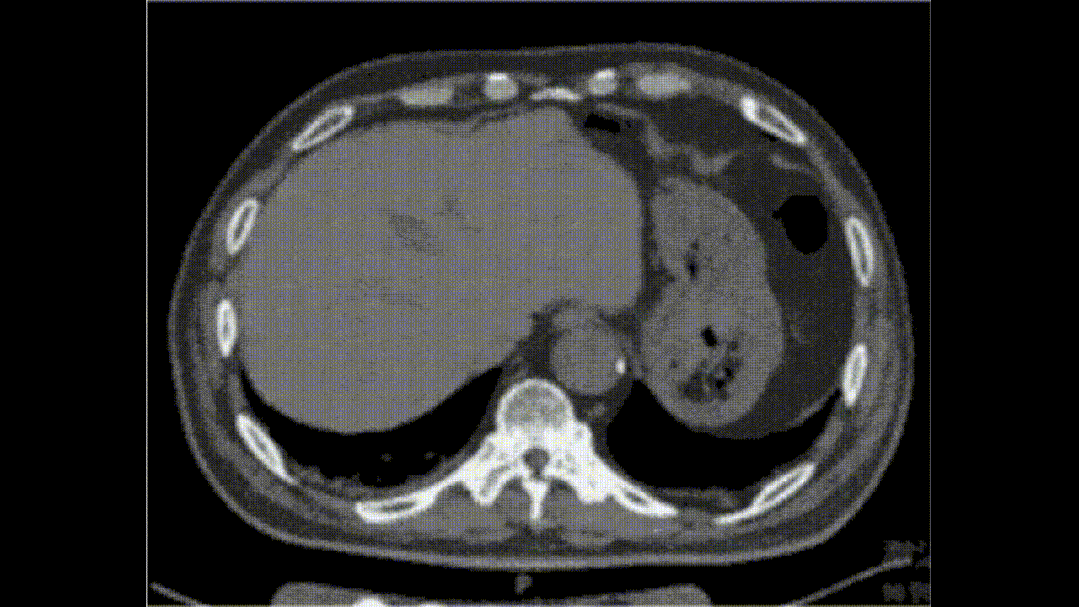

术后患者持续腹痛。术后第1天行全腹强化CT示“腹主动脉瘤术后”;结肠黏膜下多发线样气体密度影,不除外肠管积气或肠气囊肿,建议复查。

术后第9天行全腹CT平扫示:“腹主动脉瘤术后”;结肠黏膜下仍可见气体密度影,盆腔内可见多发混杂含气密度影,考虑肠坏死可能。

患者腹主动脉瘤,既往因结肠癌行右半结肠根治术。

本次EVAR术中行生物蛋白胶瘤囊填塞。

患者男,76岁,破裂腹主动脉瘤行EVAR+生物蛋白胶+弹簧圈瘤囊填塞。

术后持续腹胀,考虑腹主动脉破裂患者存在腹膜后血肿,难以鉴别是否存在严重肠缺血,术后积极随访复查CT,第18天CT提示肠穿孔,最终行结肠切除+造瘘。